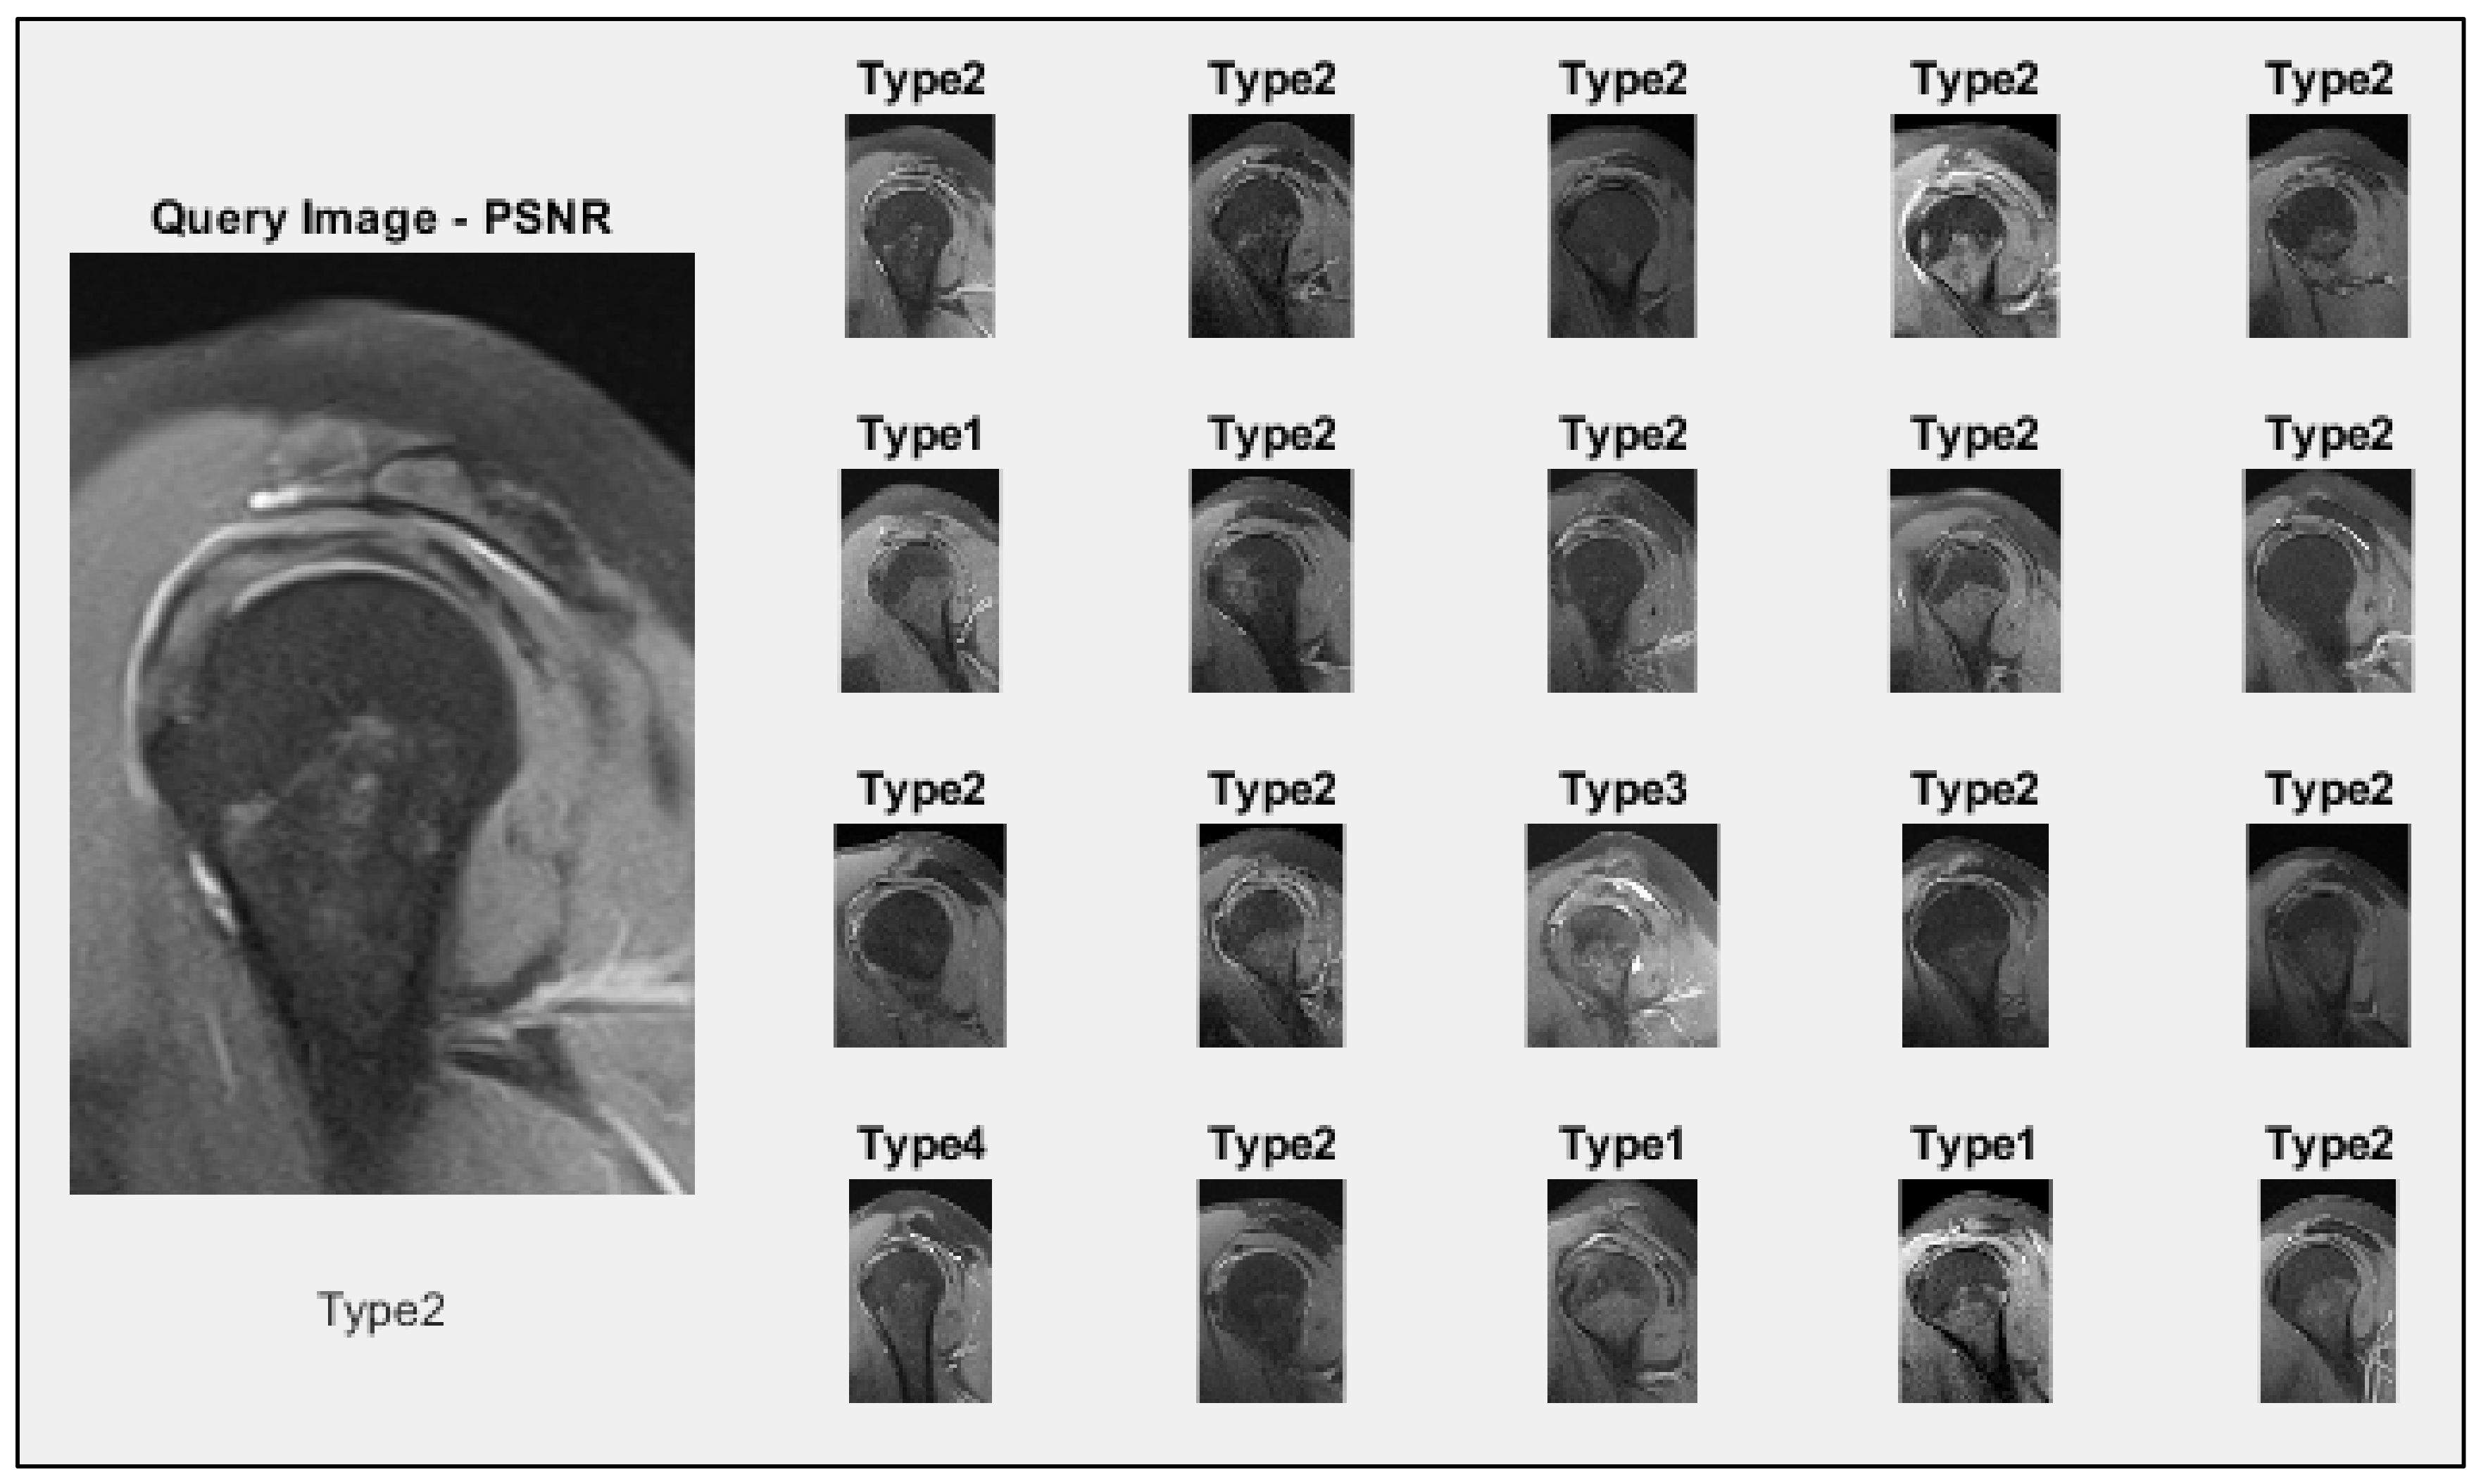

| Model | Euclidean | PSNR | ||||||

|---|---|---|---|---|---|---|---|---|

| Type 1 | Type 2 | Type 3 | Type 4 | Type 1 | Type 2 | Type 3 | Type 4 | |

| Densenet201 | 0.41 | 0.68 | 0.32 | 0.37 | 0.41 | 0.68 | 0.32 | 0.37 |

| Darknet53 | 0.43 | 0.66 | 0.33 | 0.38 | 0.43 | 0.66 | 0.33 | 0.38 |

| Efficientnetb0 | 0.41 | 0.73 | 0.37 | 0.39 | 0.41 | 0.73 | 0.37 | 0.39 |

| NasnetMobile | 0.40 | 0.69 | 0.27 | 0.30 | 0.40 | 0.69 | 0.27 | 0.30 |

| LBP | 0.40 | 0.70 | 0.36 | 0.44 | 0.60 | 0.76 | 0.63 | 0.65 |

| HOG | 0.40 | 0.71 | 0.35 | 0.49 | 0.60 | 0.77 | 0.59 | 0.67 |

| Proposed Model | 0.58 | 0.82 | 0.44 | 0.64 | 0.69 | 0.85 | 0.63 | 0.73 |